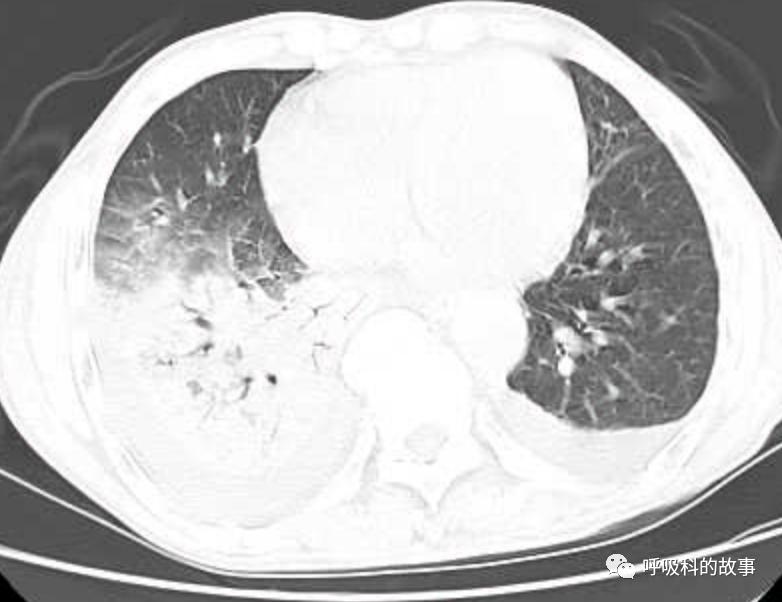

接着,我打开电脑看病历:患者,男,68岁,主诉:发热、头痛伴乏力10余天,咳嗽4天。肺部CT一看是右下叶大片实变肺炎,双侧少量胸腔积液,两上肺内中带片絮状斑片状影。2020.11.30 在外院检查 PCT 7.42ng/ml,ALT 199U/L,AST 250U/L,白蛋白24.7g/L,CRP 108.7mg/L,乳酸脱氢酶LDH388U/L(正常50-240),钾3.27mmol/L;血常规:白细胞4.9*10^9/L,中性85.2%。在外院给予了亚胺培南2天和本院美罗培南治疗2天后,效果并不理想。

(6)肺部影像以大叶性肺炎为主,其他部分是合并肺水肿的影像;